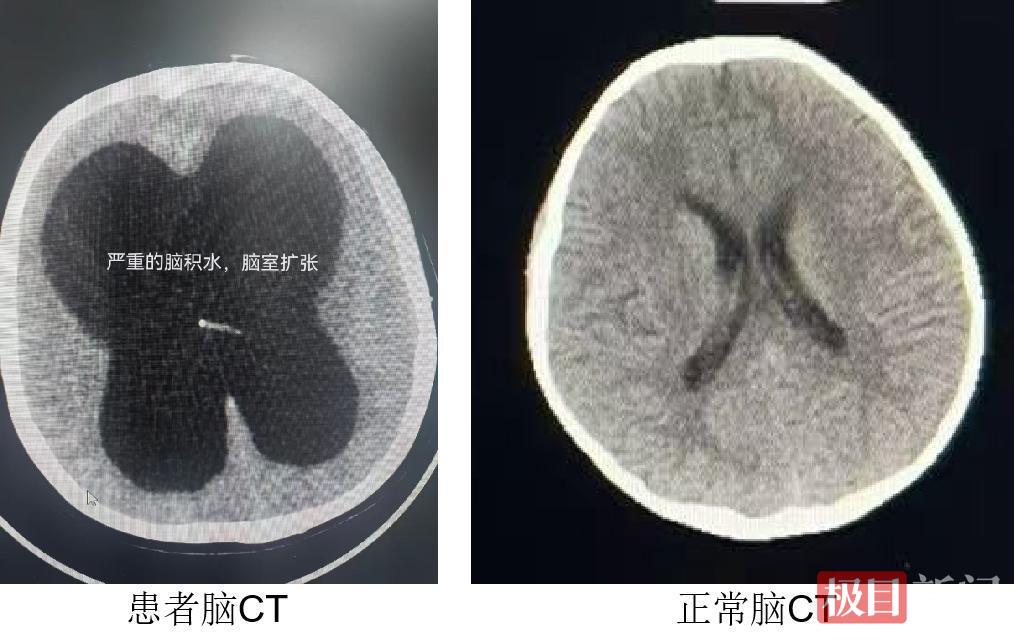

二十多年来,家人带着她寻遍了多家医院。“病情太复杂,我们无能为力”——这样的答复他们听了太多次。脑膜炎后遗症导致的严重梗阻性脑积水,让她常年被头晕头痛折磨,而近年来出现的心脏瓣膜问题,更让她的生命雪上加霜。喘气、胸闷、乏力,心力衰竭的症状日益严重,一家人陷入了绝望。

“患者脑室明显扩大,颅内压不稳定,如果先进行心脏手术,很可能引发脑水肿,影响患者苏醒,但心脏问题又刻不容缓,必须找到最佳的治疗窗口。”经过深入讨论,医疗团队最终确定了“先治脑积水、再换心脏瓣膜”的分步治疗方案——这个过程,如同拆除一枚连环炸弹,每一步都要精准无误。

邓钢教授率先为桂香实施脑室—腹腔分流术:通过在颅内植入一根细长的引流管,将多余的脑脊液引流至腹腔。手术立竿见影,长期困扰桂香的头晕头痛症状随即缓解。